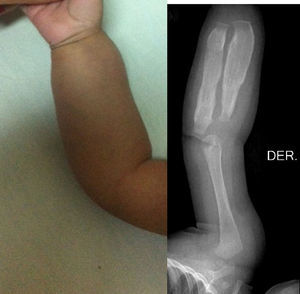

Los estudios de imágenes solicitados fueron radiografías simples de diferentes segmentos corporales, que demostraron una reacción perióstica (periostitis e hiperostosis) con cambios escleróticos, sin lesiones osteolíticas. Se apreció compromiso de la rama mandibular, el fémur izquierdo, la tibia y el radio bilateral. No se observaron microfracturas ni lesiones que involucraren metáfisis (figs. 1–4).

La enfermedad se caracteriza por neoformación perióstica y engrosamiento cortical que produce inflamación en el tejido muscular y conectivo circundantes. Se afecta la porción diafisiaria en los huesos tubulares y respeta la epífisis y la metáfisis. Puede afectar cualquier hueso, con excepción de las falanges, los cuerpos vertebrales y los huesos cuboideos12. No afecta la fisis de crecimiento13. Cuando la reacción subperióstica es muy importante entre huesos paralelos, se genera un aumento de presión y pérdida del tejido perióstico, con lo que puede ocurrir una fusión entre ambas corticales, descrito como puente interóseo. Esto puede resultar en secuelas y deformaciones óseas14; se han descrito casos de formas recurrentes15. Sin embargo, lo más frecuente es que la reacción perióstica se autolimite, se forme nuevo hueso subperióstico y el excedente de hueso periférico sea eliminado por remodelación16.

Los hallazgos radiológicos son la hiperostosis subperióstica cortical (engrosamiento perióstico) principalmente. Existe neoformación ósea subperióstica con incremento en densidad del grosor de la corteza17.